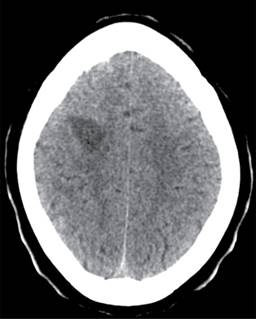

Se realizó una tomografía axial computarizada (TAC) cerebral en la que se observaron numerosas áreas hipodensas frontoparietales derechas, temporoparietales izquierdas y cerebelosas bilaterales que no realzaron tras la administración de contraste y eran compatibles con regiones de encefalitis (Figura 1).

Figura 1: Tomografía axial computarizada cerebral sin contraste, corte axial. Se visualiza una lesión hipodensa frontoparietal derecha con participación córtico-subcortical que ejerce un discreto efecto de masa correspondiente con foco de encefalitis.